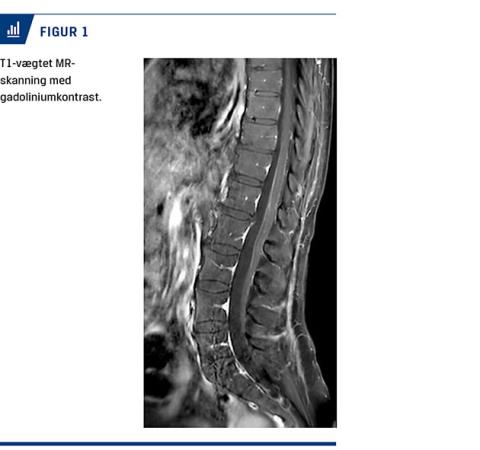

Ved en objektiv undersøgelse fandt man nedsat kraft i alle fire ekstremiteter, men mest udtalt i benene og særligt over hoften uden supranukleær fordeling. Der blev fundet ataksi trunkalt og i ekstremiteterne. Senereflekser var fraværende, og plantarresponset var normalt. Sensibiliteten var bevaret, men med allodyni distalt i underekstremiteterne. Kranienerverne var upåvirkede. Undersøgelse af cerebrospinalvæsken (CSV) viste mononukleær pleocytose på 90 × 106/l kerneholdige celler (referenceværdi: < 5 × 106/l) med 91% mononukleære leukocytter, moderat forhøjet proteinniveau på 3,23 g/l (referenceværdi: 0,15-0,50 g/l) og glukoseniveau på 3 mmol/l (referenceværdi: 2,2-3,9 mmol/l). Gentaget efter to og tre uger var der nærnormalisering af celletællingen og let forhøjet proteinniveau. Gentagne undersøgelser for herpes simplex-virus-1 og -2, varicella-zoster-virus, hiv, syfilis, hepatitis E og borrelia var negative. En polymerasekædereaktion (PCR) for TBE i CSV var negativ. Initiale serologiske undersøgelser for TBE-antistoffer i oktober var positive for immunglobulin (Ig)M, men ikke for IgG. Da undersøgelserne blev gentaget efter fire uger, var patienten positiv for IgM og IgG. En MR-skanning med kontrast af columna viste leptomeningeal kontrastopladning ved conus medullaris og filum terminale (Figur 1). En nerveledningsundersøgelse (NLU) viste svært nedsatte motoriske amplituder, moderat nedsatte sensoriske amplituder og nedsatte nerveledningshastigheder i alle fire ekstremiteter uden affektion af nn. suralis.

This is a case report of a 68-year-old woman, who developed malaise after an insect bite. Symptoms subsided, and over weeks progressing difficulty with walking, ataxia and universal areflexia developed. A lumbar puncture showed mononuclear pleocytosis and moderately raised protein levels with no detected viral agents. An MRI of the spinal cord showed leptomeningeal contrast attenuation distally. Serum samples were positive for anti-tick-borne encephalitis (TBE) IgM-antibodies, but not IgG, and showed seroconversion. TBE is endemic in areas of Central Europe and Scandinavia but has earlier only been shown in the eastern part of Denmark.